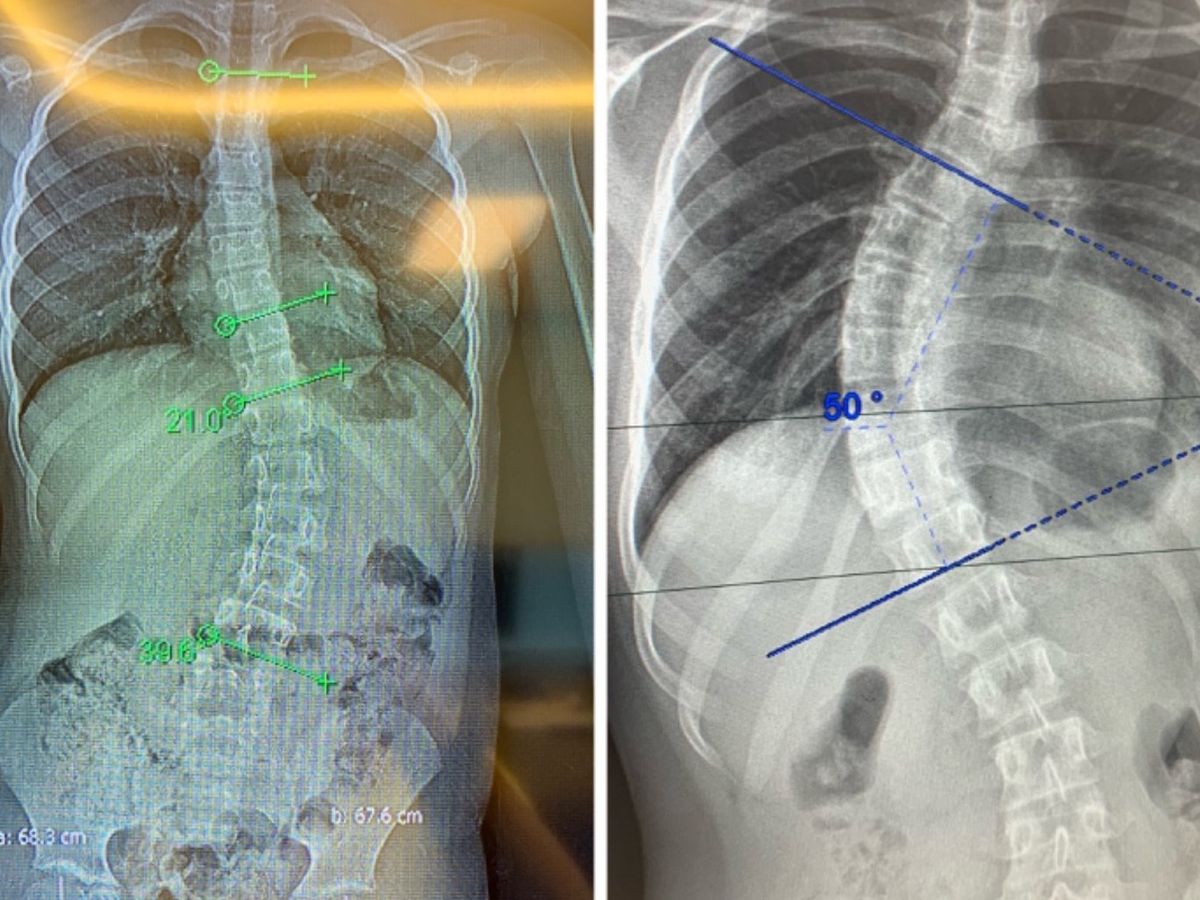

Emily was to be seen again in June but due to no clinics taking place we had to go private for a second time to be told her curve has now increased to 50 degrees with a Severe trunk shift which in turn causes her a lot of pain and discomfort. She has now been placed on the waiting list for spinal fusion surgery with no indication of waiting. How long is a piece of string???

Megan’s curves are currently sitting at 21 degrees and 39.6 degrees at the age of 10, she also hasa diagnosis of Autism and ADHD so struggles go understand the importance of wearing the braceshe has had specially made to try and slow down the progression of the curves but the likelihood of surgery in the future is high so we are continuing our fundraising efforts to ensure Megan has the same chance at a normal childhood like Emily